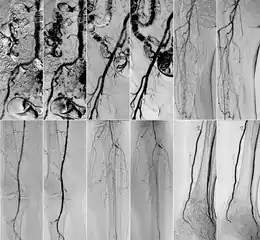

In 2018 Gyánó M. et al. compared the quality of DVA and DSA (digital subtraction angiography) images in a prospective observational crossover study, which involved the analysis of 232 image pairs of 42 patients undergoing lower limb x-ray angiography (performed by using iodinated contrast agent) between February and June 2017. Methods included the measurement of SNR (signal-to-noise ratio) and visual quality comparison.[1]

Although other factors like spatial resolution, sharpness, and object size may contribute to image quality and object perceptibility, noise places a fundamental limitation on the ability to recognize structures on low-contrast images and that was the main reason why the SNR measurement method was chosen. The results showed 2-3 times higher SNR values in the case of DVA images compared to traditionally used DSA images, which has indicated that DVA has the potential to improve the ability to view blood vessels, since a higher SNR value indicates lower noise levels.

Qualitative comparison has been performed by three vascular surgeons and three interventional radiologists, with about 17 years of experience on the average. In an online visual questionnaire, which showed DVA and DSA image pairs of the same anatomical regions, raters were asked to choose the image which they found to be more useful for making the diagnosis. Overall, the raters judged the kinetic images better in 69% of all images. Regarding different anatomical regions, the raters agreed that the DVA was significantly better for talocrural and popliteal regions.

Since the SNR is proportional to radiation dose, the authors have concluded that the higher SNR values indicate that the DVA method has the ability to generate angiographic images which have the same quality as the currently used DSA, but the dose of the administered radiation and/or contrast media could be lowered to achieve the same vessel visibility.